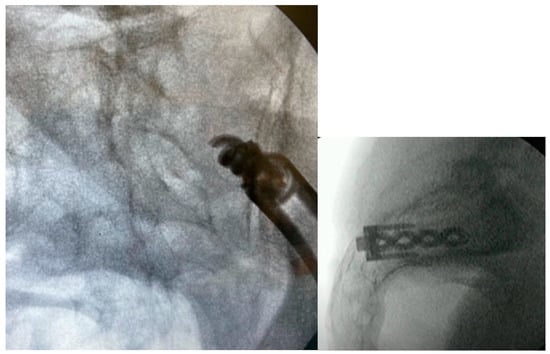

3.3.2. Intraoperative Imaging

3.3.9. Final Implant Placement